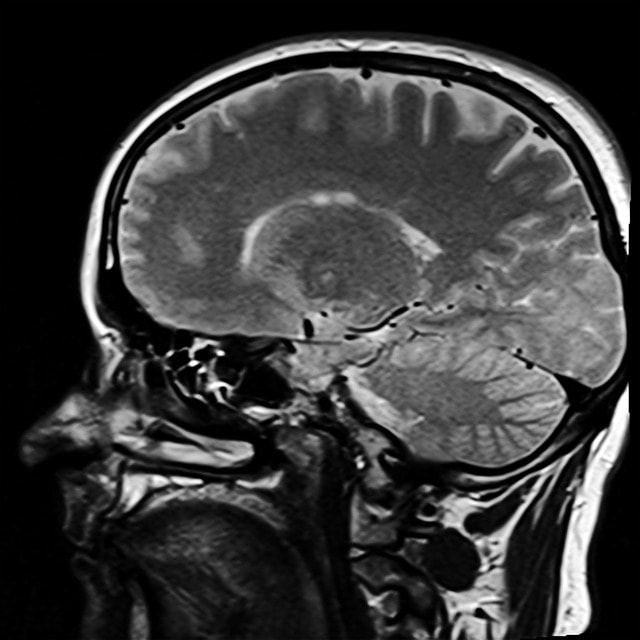

En tyst stroke, eller tyst infarkt, ger inga tydliga symtom men kan ändå skada hjärnan. Vid en tyst stroke saknas de typiska, akuta symptomen, vilket innebär att personen inte märker av stroken när den sker. Med datortomografi kan läkare skapa detaljerade tvärsnittsbilder av hjärnan för att identifiera tecken på tyst stroke.

Läkaren kan se ‘vita fläckar’ eller skador i hjärnvävnaden som indikerar att en infarkt har skett. Undersökningen hjälper också till att identifiera andra möjliga orsaker till symtomen, som en hjärntumör, hjärnblödning eller blödning.

Magnetkameraundersökningar (MRT) kan ibland komplettera datortomografi för en mer noggrann diagnos. Vid osäker strokediagnos efter datortomografi gäller särskilda riktlinjer och ibland rekommenderas att MRT med diffusions-sekvenser görs. Kombinationen av dessa metoder säkerställer korrekt diagnos och behandling av tysta stroke symptom.

MRT använder magnetfält och radiovågor för detaljerade bilder av hjärnans struktur och funktion. Det hjälper läkare att förstå skador och planera behandling.

Tyst stroke upptäcks vanligtvis med hjälp av datortomografi (DT) eller magnetresonanstomografi (MRT), som kan visa skador eller ”vita fläckar” i hjärnvävnaden.